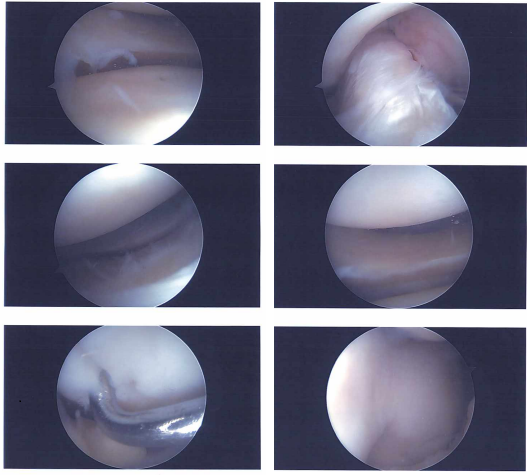

Case Study: Knee Arthroscopic Meniscectomy, Microfracture Chondroplasty and Arthroscopic Assisted Tibial Plateau Fixation with Calcium Phosphate Cement (Subchondroplasty)

Microfracture (Meniscus Repair, Knee Scope), Meniscectomy Knee arthroscopy is the process of using an arthroscope to look for general damage to the knee’s tissues and to heal specific ailments.

Status post right knee arthroscopic meniscectomy, microfracture chondroplasty and arthroscopic assisted tibial plateau fixation with Calcium phosphate cement (subchondroplasty) surgery performed. She is also status post left shoulder Arthroscopic Surgery performed.